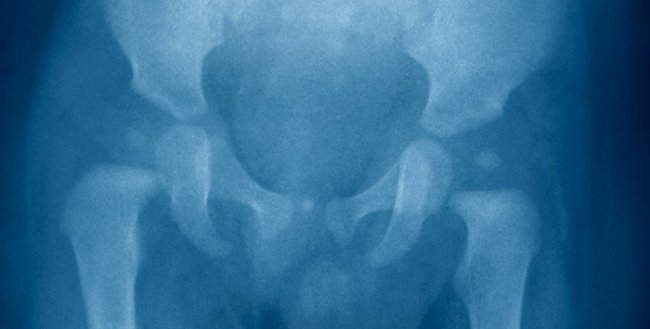

Рентгенография. Может оказаться полезной для диагностики дисплазии тазобедренного сустава у детей в возрасте 4–6 месяцев. У более юных младенцев она малоинформативна, так как головка бедренной кости и вертлужная впадина еще не окостенели и потому не контрастируются на снимках.